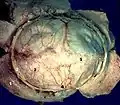

The course and connections of the facial nerve in the temporal bone. Human brain dura mater

Human brain dura mater